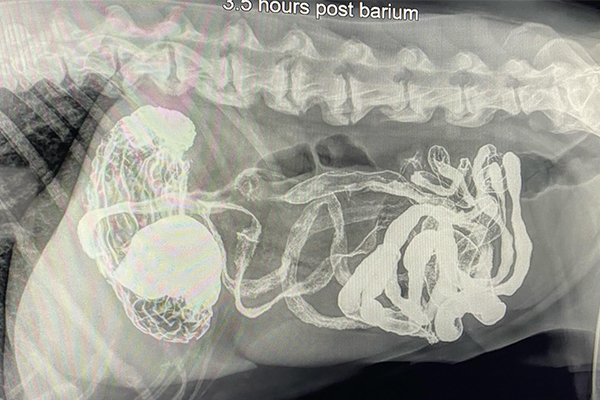

Barium Series

This procedure is a Contrast Study which means that we use a contrast dye that shows up on x-ray and highlights certain structures. Because some objects don’t show up on xray (plastic, fabric, toys, etc), this can help outline it or show us where the obstruction is as it can’t get past.

Our talented Registered Veterinary Technicians administer barium (the contrast liquid) in the mouth and then we take successive X-rays over the next few hours to watch its progress. The first X-ray is almost immediate to catch the outline of the esophagus while the last one may be hours later as it enters the colon .

Flip through the photos to see the progression of barium through the gastrointestinal tract: